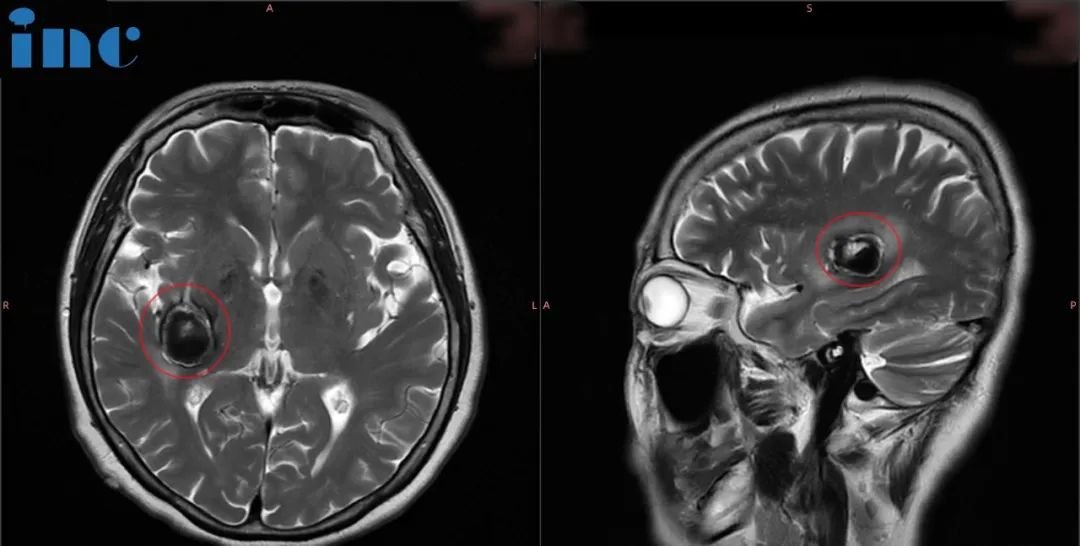

然而谁也没想到9月底教授在华手术期间柯女士症状开始出现波动,发作频繁。2023年9月5号再次核磁,病灶又增大了,除了原来各种麻的症状,我又感觉这个脸、耳朵都疼,麻、胀……症状又加重了。

当巴教授查看核磁图像后,发现病灶较前增大,结合患者病情有进展,告知患者随时会有出血风险,需要立即手术。柯女士和家人与巴教授紧急视频沟通之后,决定提前手术,果断买飞机票来到苏州。9月29日视频会议,30日早晨从东北飞过来,10月1日成功手术。柯女士一家人终于松了一口气,这个困扰他们已久的问题终于得到的解决。

术后核磁显示,海绵状血管瘤得到顺利全切,柯女士的状态也好,神采奕奕,和常人无异。